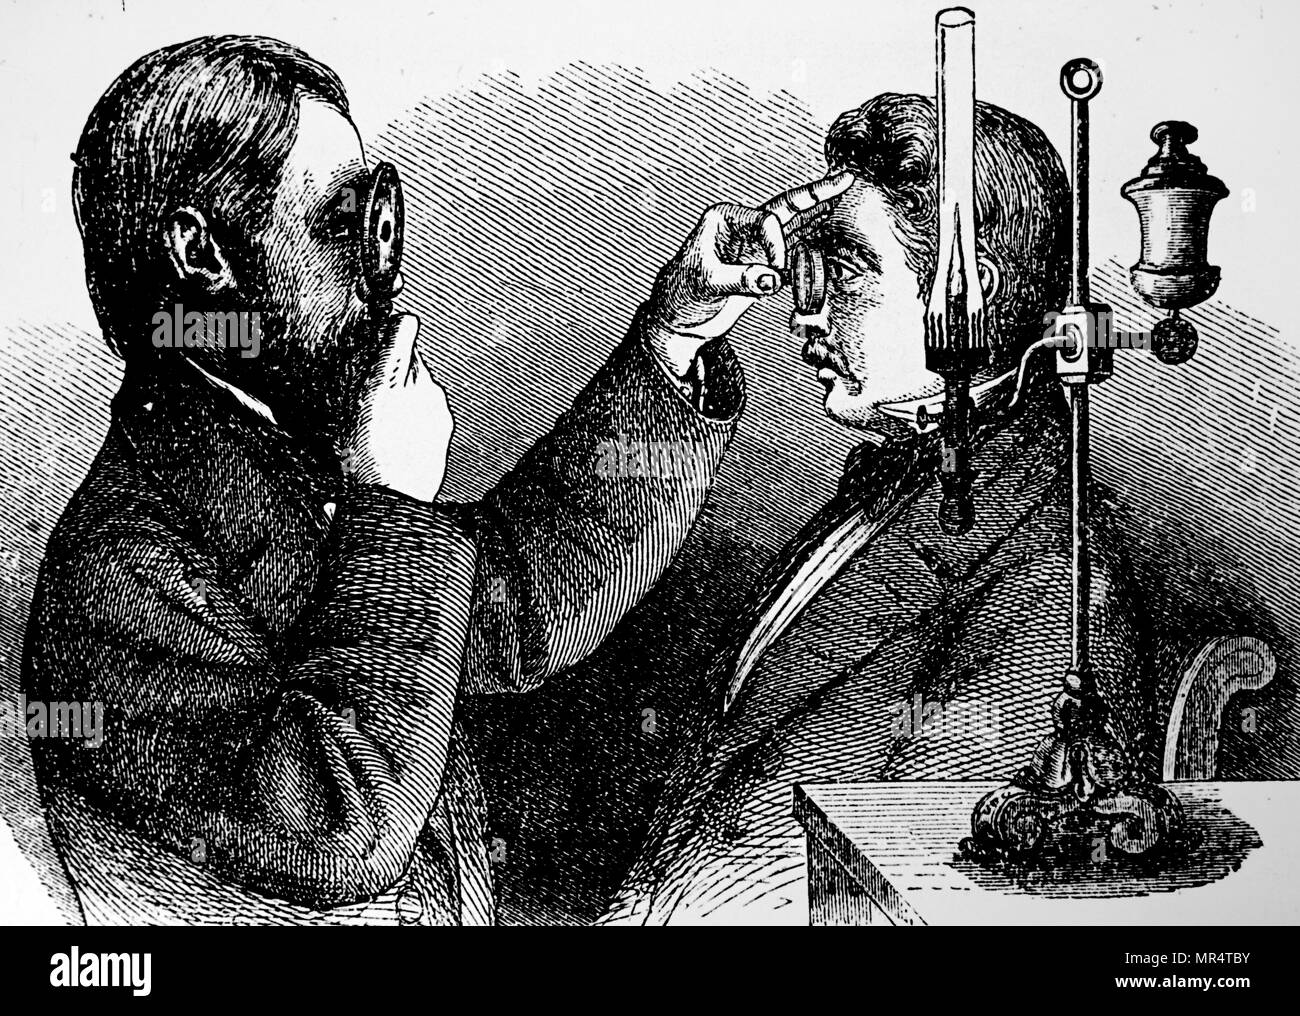

Engraving depicting an ophthalmoscope in use. Ophthalmoscopy, also called funduscopy, is a test that allows a health professional to see inside the fundus of the eye and other structures. The ophthalmoscope was invented by Hermann von Helmholtz (1821-1894) a German physician and physicist. Dated 19th century Stock Photohttps://www.alamy.com/image-license-details/?v=1https://www.alamy.com/engraving-depicting-an-ophthalmoscope-in-use-ophthalmoscopy-also-called-funduscopy-is-a-test-that-allows-a-health-professional-to-see-inside-the-fundus-of-the-eye-and-other-structures-the-ophthalmoscope-was-invented-by-hermann-von-helmholtz-1821-1894-a-german-physician-and-physicist-dated-19th-century-image186347727.html

Engraving depicting an ophthalmoscope in use. Ophthalmoscopy, also called funduscopy, is a test that allows a health professional to see inside the fundus of the eye and other structures. The ophthalmoscope was invented by Hermann von Helmholtz (1821-1894) a German physician and physicist. Dated 19th century Stock Photohttps://www.alamy.com/image-license-details/?v=1https://www.alamy.com/engraving-depicting-an-ophthalmoscope-in-use-ophthalmoscopy-also-called-funduscopy-is-a-test-that-allows-a-health-professional-to-see-inside-the-fundus-of-the-eye-and-other-structures-the-ophthalmoscope-was-invented-by-hermann-von-helmholtz-1821-1894-a-german-physician-and-physicist-dated-19th-century-image186347727.htmlRMMR4TBY–Engraving depicting an ophthalmoscope in use. Ophthalmoscopy, also called funduscopy, is a test that allows a health professional to see inside the fundus of the eye and other structures. The ophthalmoscope was invented by Hermann von Helmholtz (1821-1894) a German physician and physicist. Dated 19th century